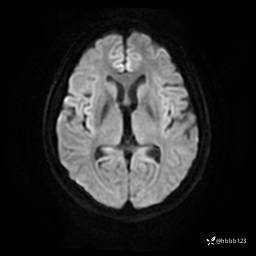

DWI: